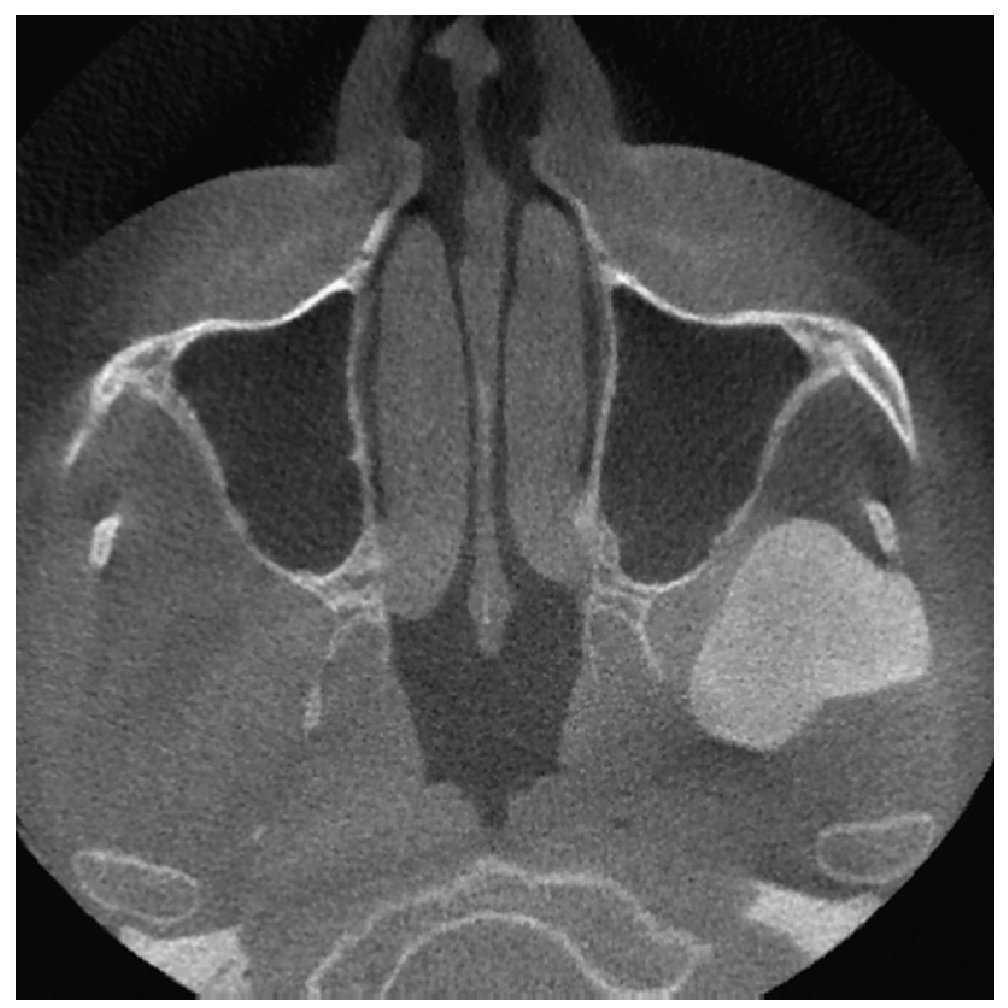

La radiografía panorámica (fig. 1) mostró una estructura de tejido óseo, densa, homogénea, con forma de hongo, bordes bien definidos y un diámetro de varios centímetros. La lesión parecía originarse en un área por encima del agujero mandibular. Un TAC de haz de cono (figs. 2 a 5) reveló la presencia de una lesión homogénea osteodensa de 3 x 3 x 2,7 cm que crecía a partir de un pedúnculo en la cara lingual de la escotadura mandibular. La circunferencia anterior alcanzaba casi a la apófisis coronoides.

Figura 1. Radiografía panorámica.